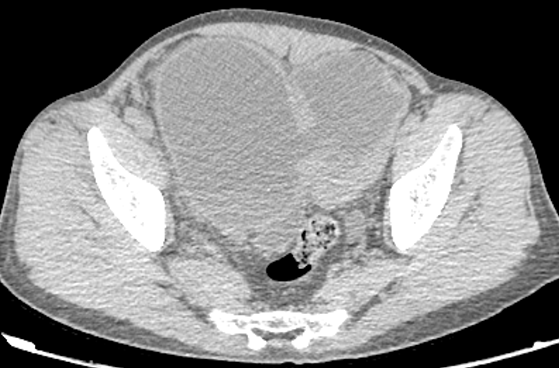

病例一

患者,男,34 岁,因尿频、尿急、尿痛 3 周,间断右侧腰痛伴发热 2 周入院。体温最高 38℃,入院查血白细胞增高。

膀胱壁弥漫性增厚、毛糙,周围脂肪间隙浑浊,腔内未见异常密度影。腹膜后及盆腔脂肪间隙广泛浑浊。

好发部位位于膀胱三角区及膀胱颈部,CT 表现为膀胱壁增厚、隆起性病变,多>5 mm,宽基底,病灶边缘光滑,隆起内可见囊变或钙化。增强后轻度强化,较邻近正常膀胱壁密度相似,膀胱外壁光整,局部输尿管壁可受累,一般无盆腔淋巴结肿大。影像学分型:草坪型-膀胱壁内节段性增厚;弥漫型-膀胱壁弥漫性增厚;结节型-膀胱内壁结节样隆起,表面光整、宽基底(钝角)。本病例 1 属于弥漫型,病例 2 属于草坪型。